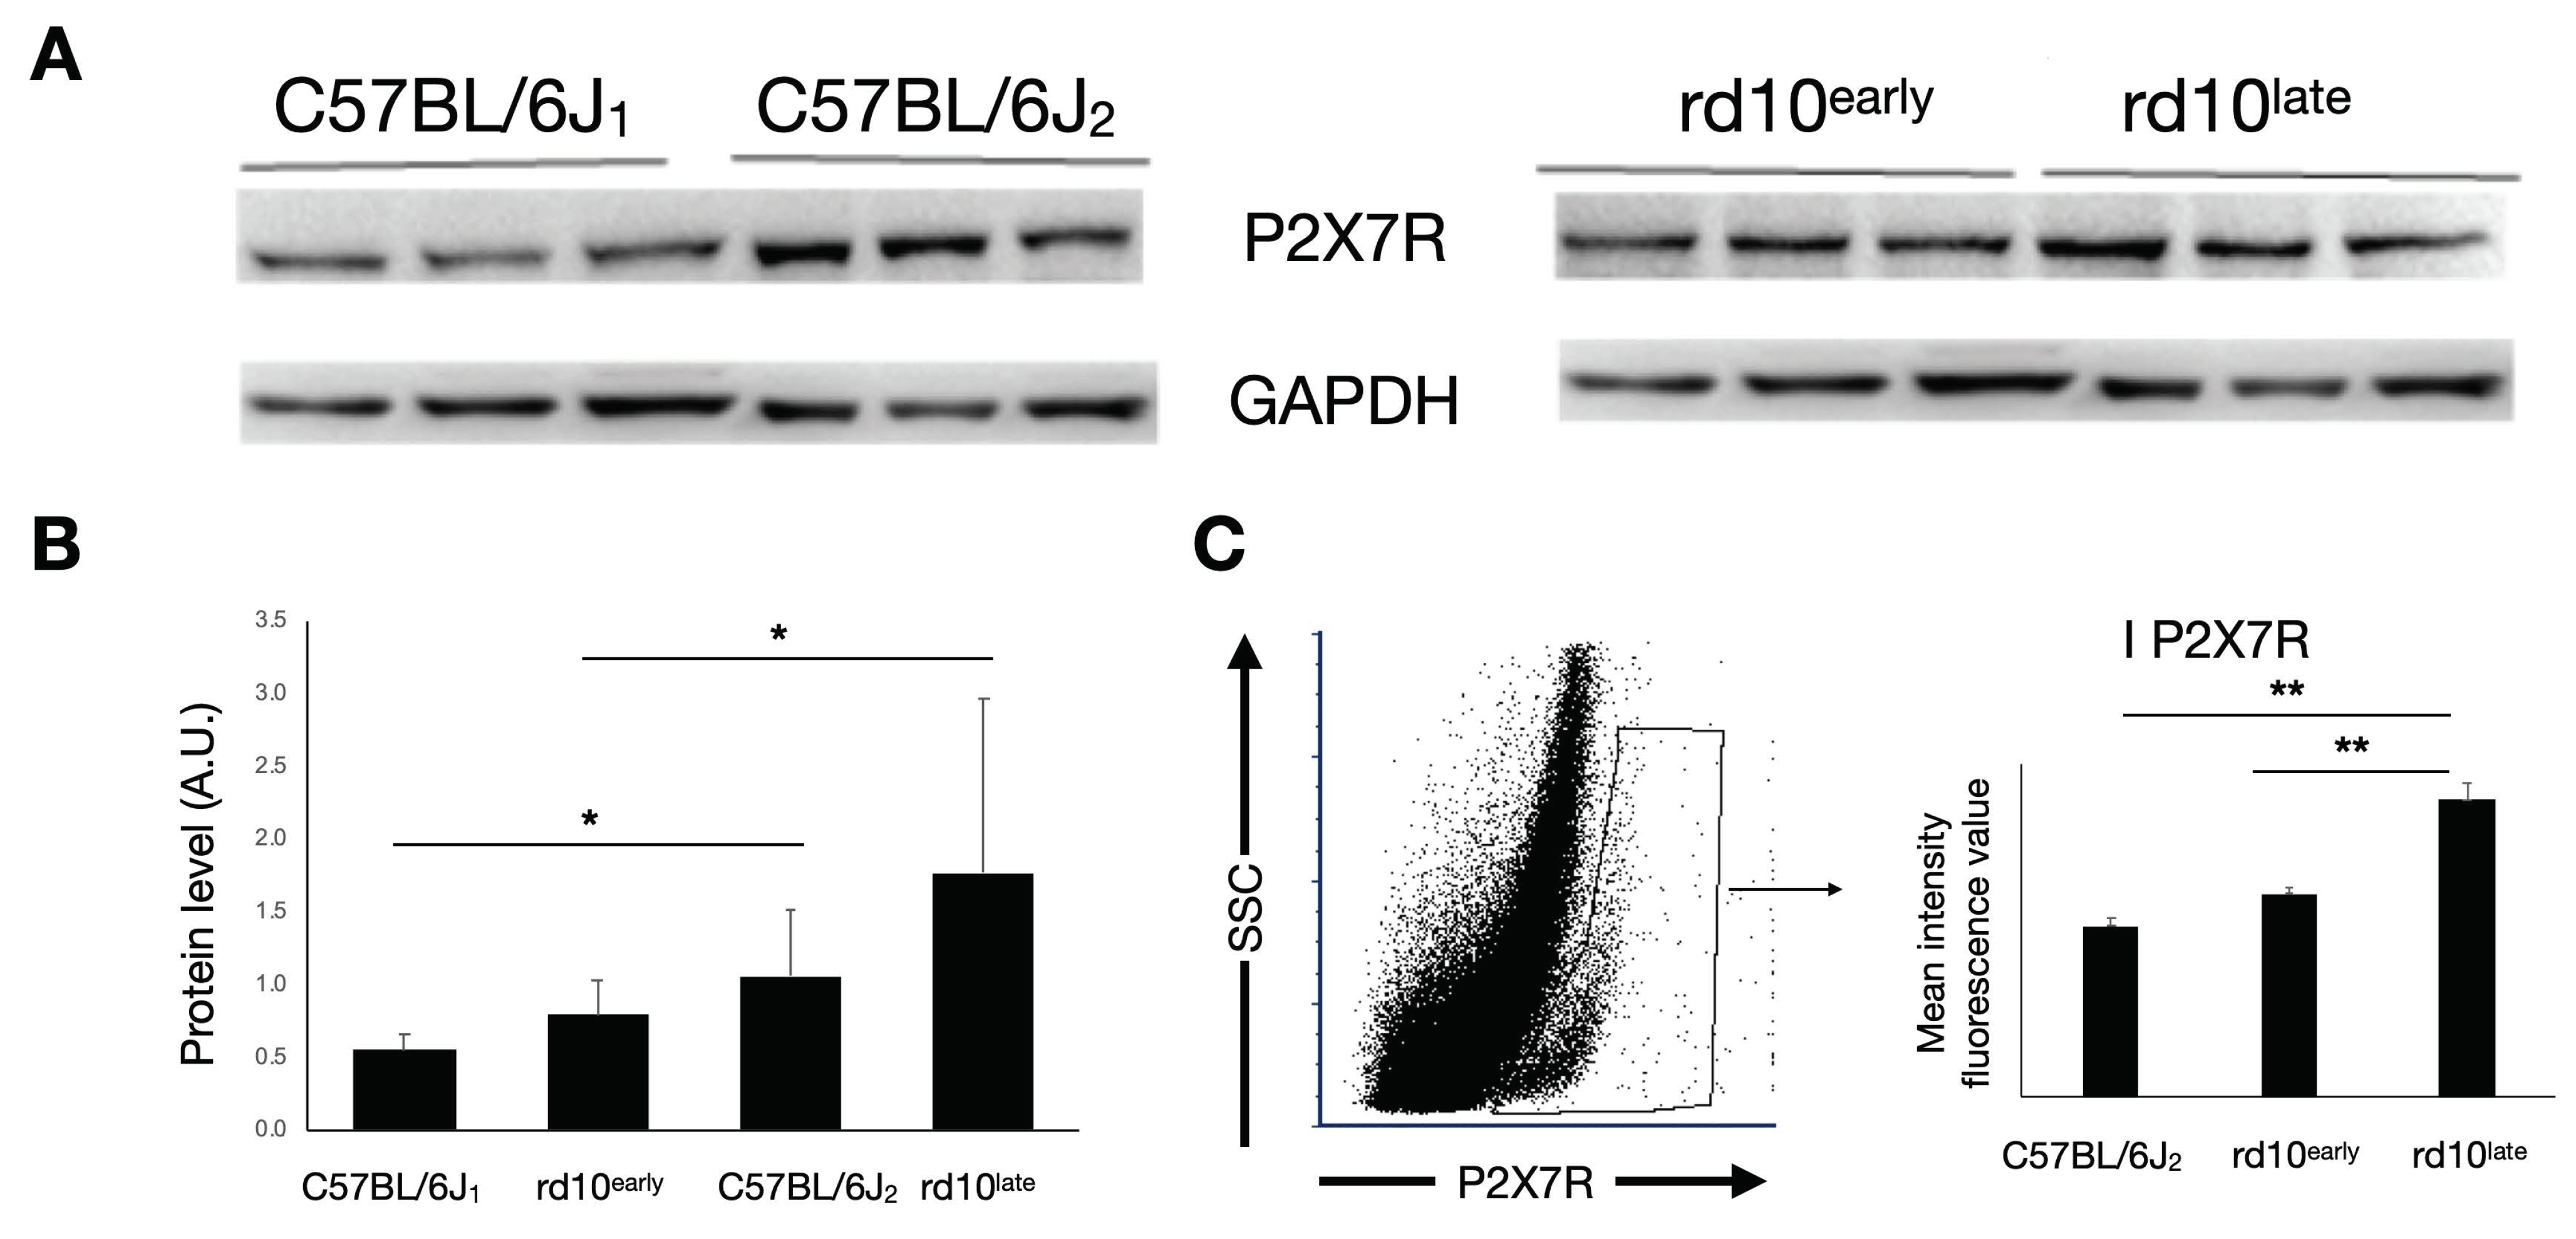

2.2. P2X7R Expression in rd10 Mice